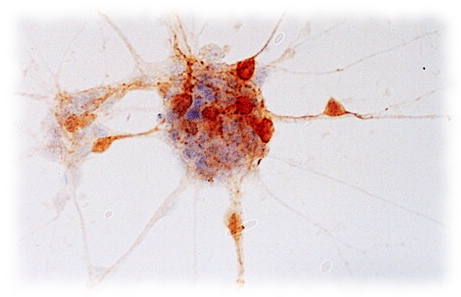

We are a company dedicated to developing neutralizing antibodies that can be used as a treatment for novel viruses. Our team is working on improving methods for rapid screening and cloning of cells that produce high-affinity antibodies for use in clinic. While developing virus-specific drugs can take long time, neutralizing antibodies can be produced relatively quickly making them an excellent first choice of treatment until the vaccine or antivirals are available.

- Human neutralizing antibodies for treatment.

- Mouse monoclonal antibodies for research.